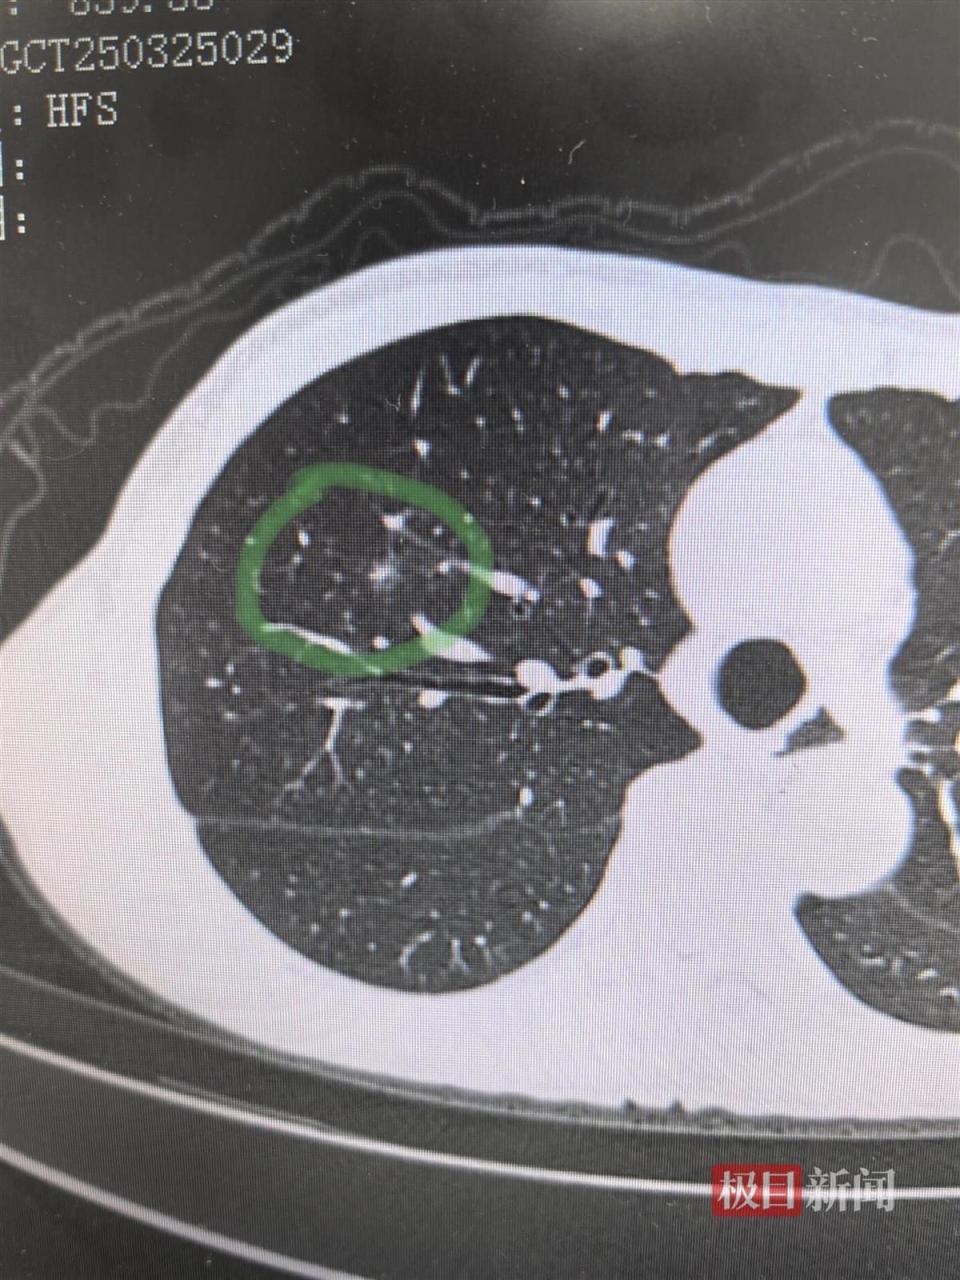

该院胸外科主任张倬接诊后,为其进行了详细的检查,CT结果提示为右上段肺部存在一个7毫米的部分实性结节,不排除原位/微浸润腺癌。随后,胸外科与放射科充分研判讨论,决定利用三维重建技术重建刘婆婆的肺部模型、肺结节三维详细分布图,制定术前规划及手术方案。

图片影像提示右肺上段存在肺结节